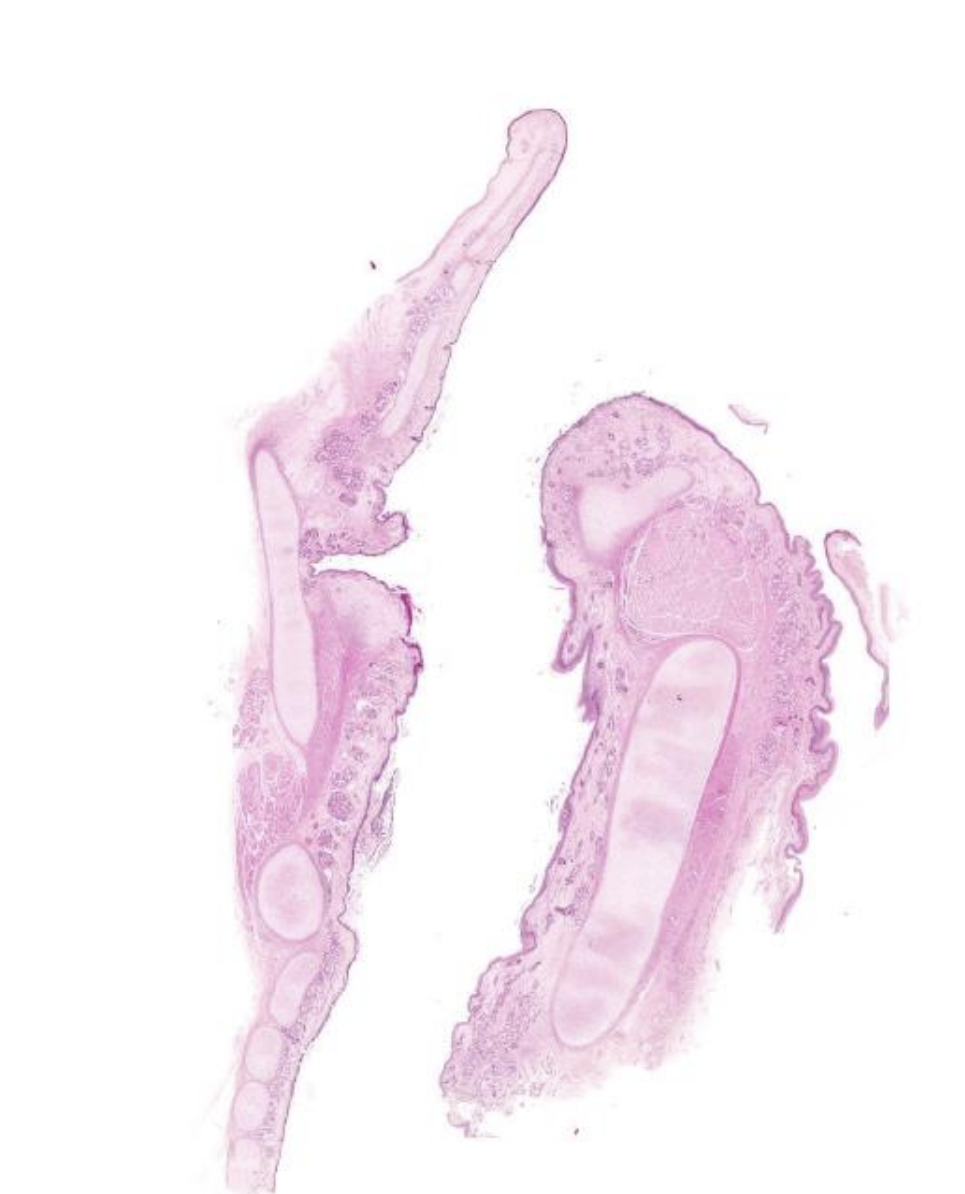

False Vocal (or Ventricular) Fold

Respiratory Epithelium - pseudostratified columnar epithelium with cilia and goblet cells.

Pseudostratified Columnar Cells - basal bodies visible as a dark line at the base of the cilia.

Goblet Cells - clear, oval structures with heterochromatic nuclei adjacent to ciliated, columnar cells.

Basement Membrane - an amorphous thick, pink band at the base of the epithelium.

Sero-Mucous Glands - add moisture to air and aid in trapping contaminants.

Laryngeal Ventricle - a lateral diverticulum that separates false folds above from true vocal cords below.

True Vocal Cord

Vocal Ligament - thick band of connective tissue within the lamina propria near the surface of the vocal cord.

Stratified Squamous Non-Keratinized Epithelium - covers this region of the larynx because it is subject to mechanical stress.

Vocalis Muscle - skeletal muscle that underlies and regulates the tension of the vocal ligament.

Respiratory Epithelium - covers the true vocal cord except for the region that covers the vocal ligament.